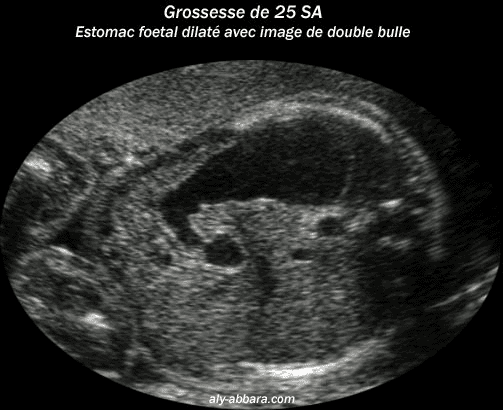

Grossesse de 25 semaines d'aménorrhée avec la mise en évidence d'un estomac dilaté et image de double bulle

Il s'agit d'une sténose duodénale partielle (le liquide amniotique est resté en quantité normale durant la grossesse)

L'intervention post-natale met en évidence la présence d'un diaphragme duodénal avec pancréas annulaire nécessitant

une anastomose latéro-latérale en diamant.

Caryotype normal.